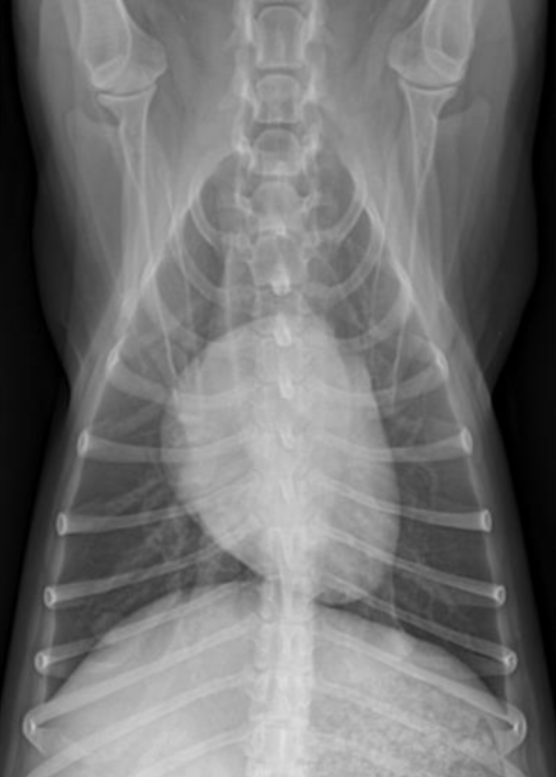

| DV (Dorso-ventral) | VD (Ventro-dorsal) |

![]() | ![]() |

| ์ฌ์ฅ ๊ด์ฐฐ์ ์ข์. | ํ ๊ด์ฐฐ์ ์ข์. |

| ๊ธฐํ ์์ ๋ ์ข์. (pleural air) | ํ์ ์์ ๋ ์ข์. (pleural fluid) (๋ฐ๋ฅด๊ฒ ๋์ธ ์ผ๊ฐํ ๋ชจ์ - ํ์๊ฐ ์๋-์์ผ๋ก ํผ์ง) |